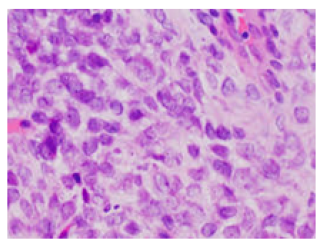

A The Stringy Emend-BCOR Rearranged Sarcoma

Anubha Bajaj. 22(7): 41-45.

Teensy and Orbed-CIC Rearranged Sarcoma

Anubha Bajaj. 22(7): 01-05.